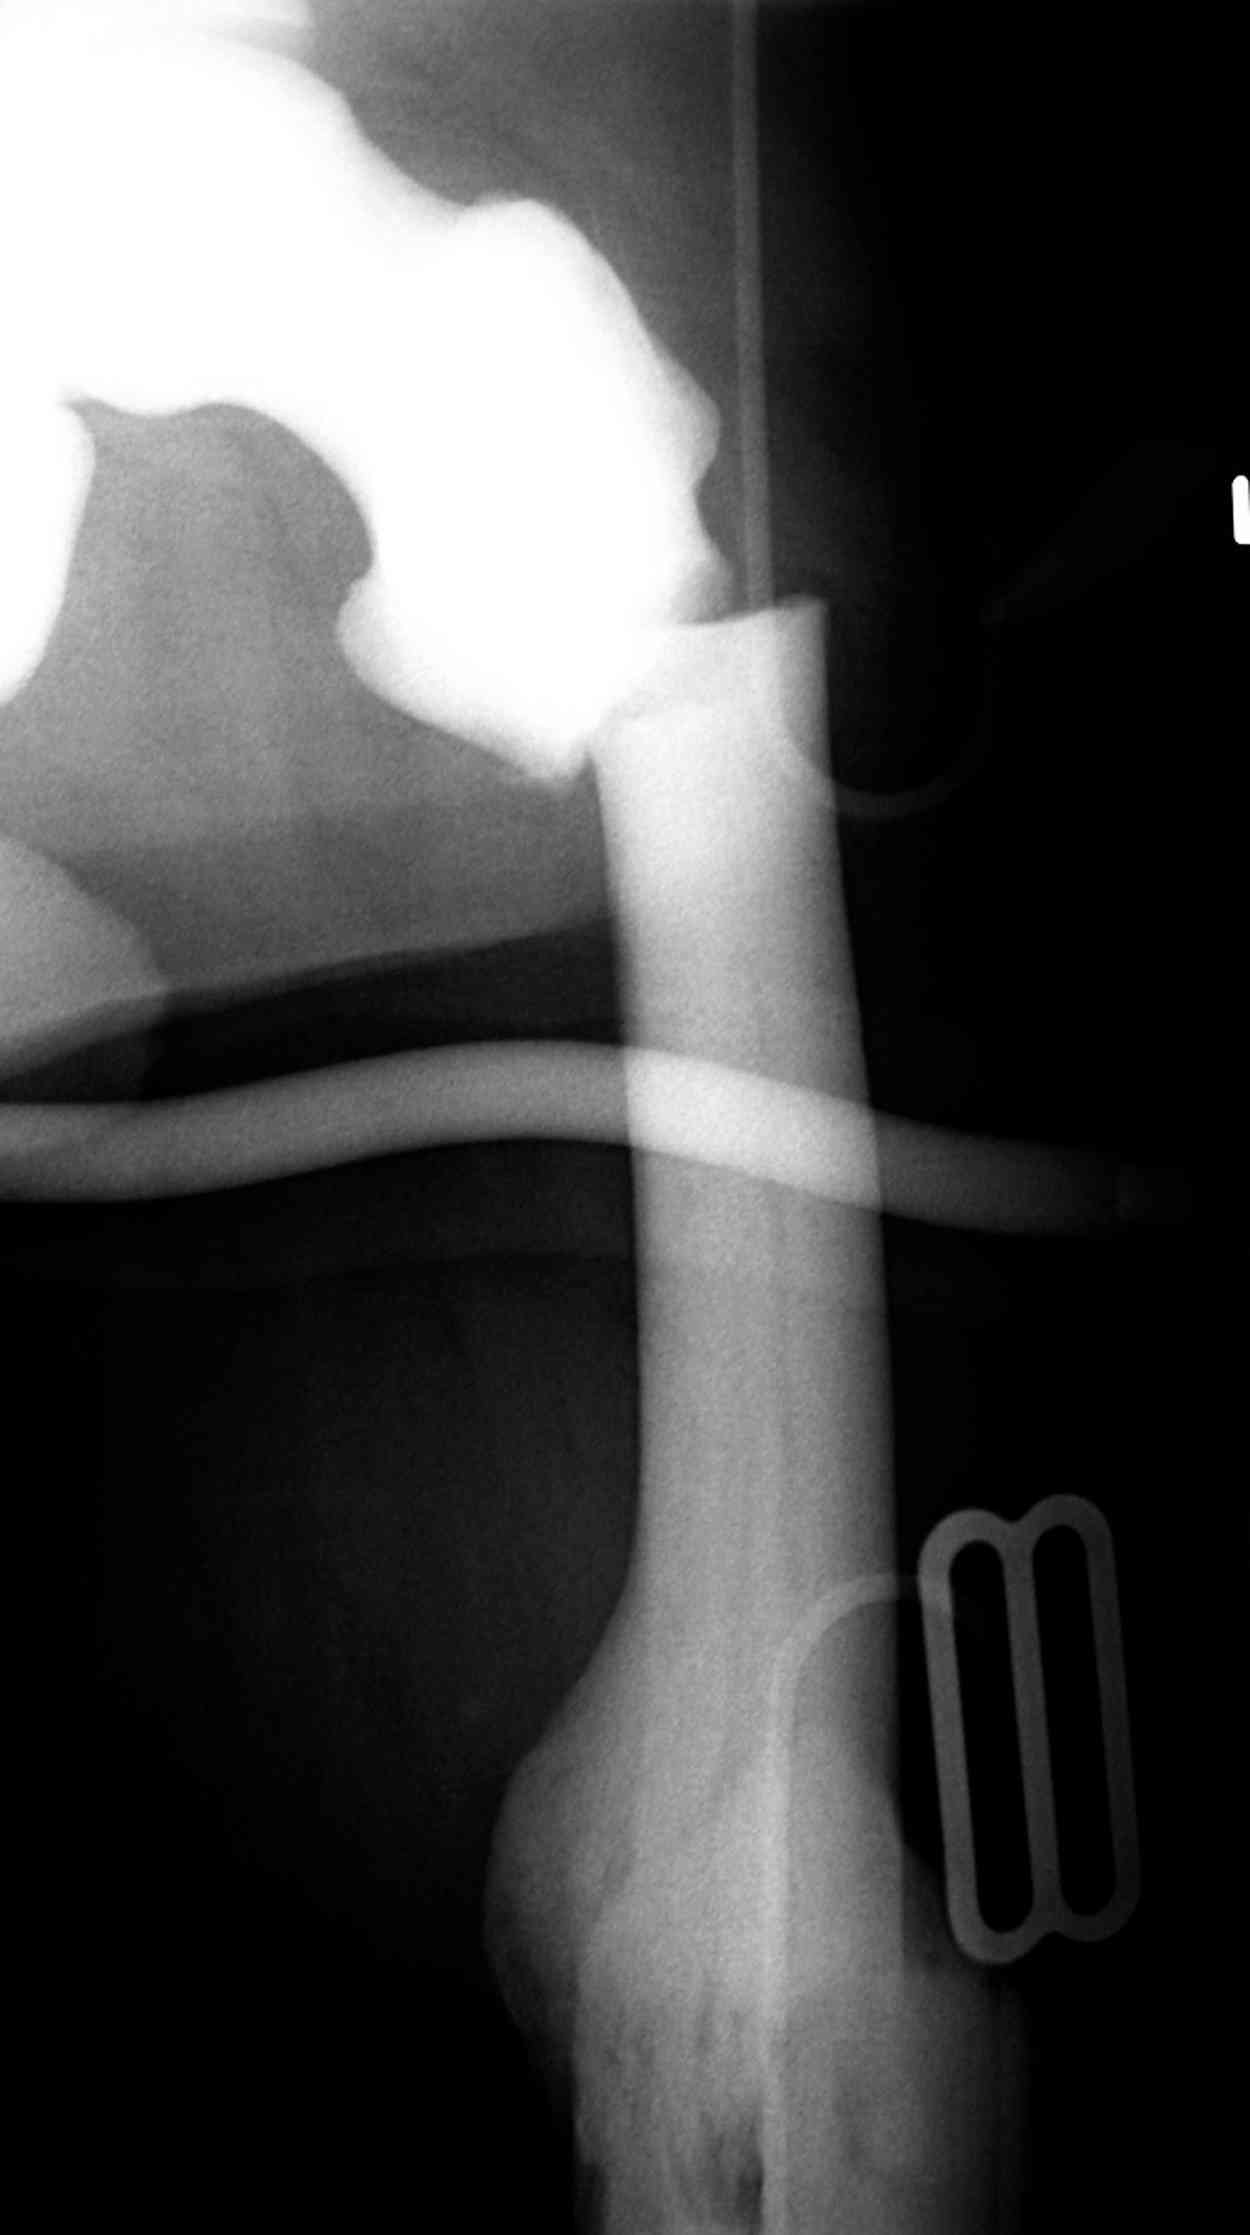

Здесь у меня дополнительные снимки с большим разрешением и в разных режимах, а то те дигитал снимки совсем очень блеклые, может, эти изображени изменят выбор тактики

Не вызывает ли подозрение, что отсутствует медуллярный канал, как просверлить канал?

Канал, возможно, действительно запаян. Но разве большие проблемы его создать и рассверлить (если только это мраморная болезн?) Уверен, в вашей клинике есть для этого всё.